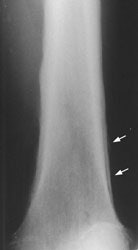

New Criterion for Determination of Pathologic Hilar Adenopathy

Example 1: This is an example of an N1 node in a patient with a lingular adenocarcinoma (left image). Although not pathologic by short axis size criteria, the lymphatic tissue in the left hilum has a convex border with the adjacent lung (white arrows). This node contained adenocarcinoma at histopathologic analysis. Some authors advocate using the presence of a convex margin of the interstitium with the lung parenchyma to indicate pathologic adenopathy to improve the sensitivity of CT for detecting hilar metastases [36].

NOTE: Click image to enlarge